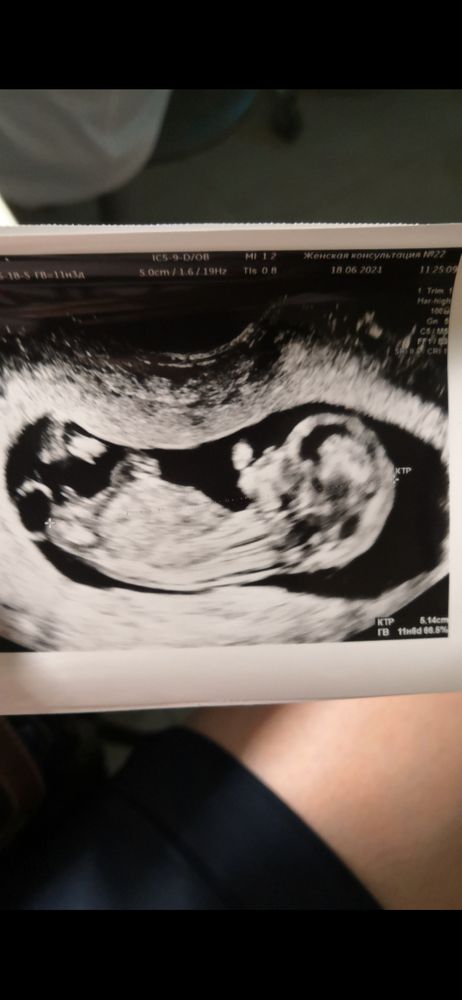

Киста хориона.И угадай пол🤭

Очень переживаю по поводу этой кисты хориона.Особенно по поводу прикрепления пуповины к этой перегородке🙈УЗИсты говорят смотреть в динамике в 16 недель😎

Может кто-то знает похожие истории,как это может повлиять на исход беременности?Давайте хорошие истории🙏

Даже за потерявшиеся почки на первом скрининге меньше переживаю🙄

И кто тут у нас спец по определению пола,как думаете,кто это?🥰